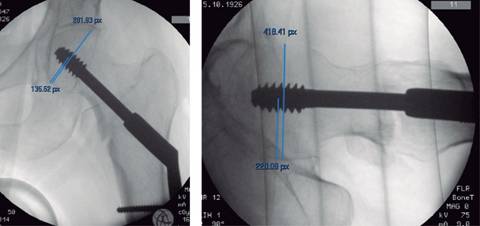

El índice punta ápice mayor se medirá en milímetros según el método descrito por Baumgaertner (Figura 1).

Figura 1: Índice punta ápice mayor. Método introducido por Baumgaertner en 1995; toma en cuenta la profundidad y el sitio de colocación del tornillo. Se deben sumar las dos distancias en las proyecciones anteroposterior y lateral; si al ser sumadas son 25 mm o más, está incrementado el riesgo de fallo. En este ejemplo, se realizó un ajuste para un tornillo de 90 mm; se obtuvo en AP 5.89 mm y en lateral 6.6 mm; se consiguió un TAI de 12.4 mm.3,4,5,9,18,19,20